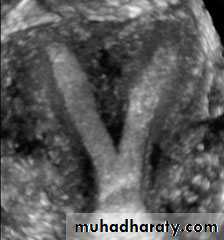

• Uterus

• Reconstructed coronal view of the uterus demonstrating cornuas (arrow) and cervix, with a normal uterine contour